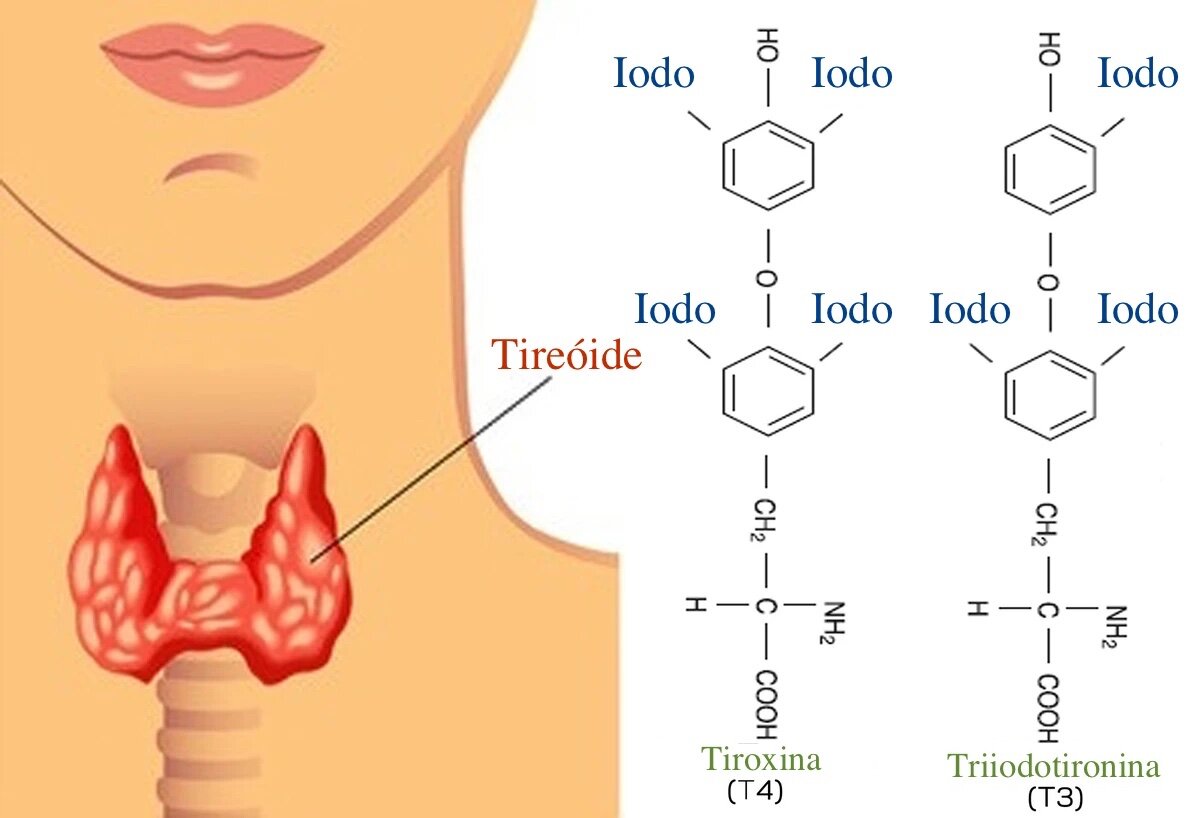

Olha só que interessante: sua tireoide é tipo uma fábrica de hormônios. Para produzir T3 e T4, que são os maestros do seu metabolismo, ela precisa de uma matéria-prima chave: o iodo.

Essa captação de iodo direto do sangue é o primeiro passo para que esses hormônios sejam sintetizados.

Sem iodo suficiente, a ‘fábrica’ simplesmente não consegue trabalhar direito, impactando diretamente como seu corpo usa energia para tudo, desde pensar até se movimentar.

“O iodo é um mineral essencial cuja única função fisiológica conhecida no corpo humano é a síntese dos hormônios tireoidianos (T3 – tri-iodotironina e T4 – tiroxina) pela glândula tireoide, fundamentais para regular o metabolismo e o desenvolvimento de órgãos, especialmente o cérebro.”

O Papel do Iodo na Produção de Hormônios Tireoidianos (T3 e T4)

A tireoide tem um trabalho árduo: produzir os hormônios T3 (triiodotironina) e T4 (tiroxina). E para fazer isso, ela precisa de um parceiro essencial: o iodo. A tireoide capta o iodo do sangue e o utiliza em um processo bioquímico complexo para formar esses hormônios. O T4 tem um átomo de iodo a menos que o T3 e é mais abundante, servindo como um reservatório que pode ser convertido em T3 conforme a necessidade do corpo.

Esses hormônios, T3 e T4, são como os maestros da nossa orquestra metabólica. Eles ditam a velocidade com que nossas células realizam suas funções, influenciando desde a queima de calorias até a produção de proteínas e a manutenção da temperatura corporal. A quantidade de iodo disponível impacta diretamente a capacidade da tireoide de produzir a quantidade certa desses hormônios.